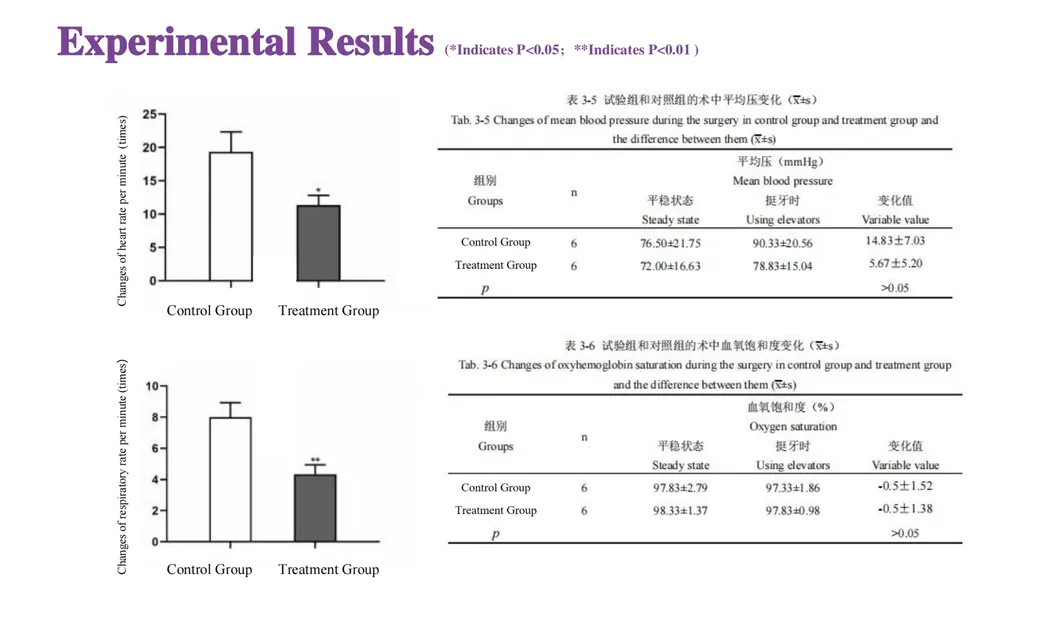

This study evaluated the effectiveness of state-of-the-art dental tools for veterinary use. The treatment group utilized the revolutionary Pneumatic Dental Elevator Kit. Critical factors observed included physiological parameters, intraoperative complications, extraction duration, and socket damage. Rigorous statistical analysis highlights the superior performance of these advanced tools.